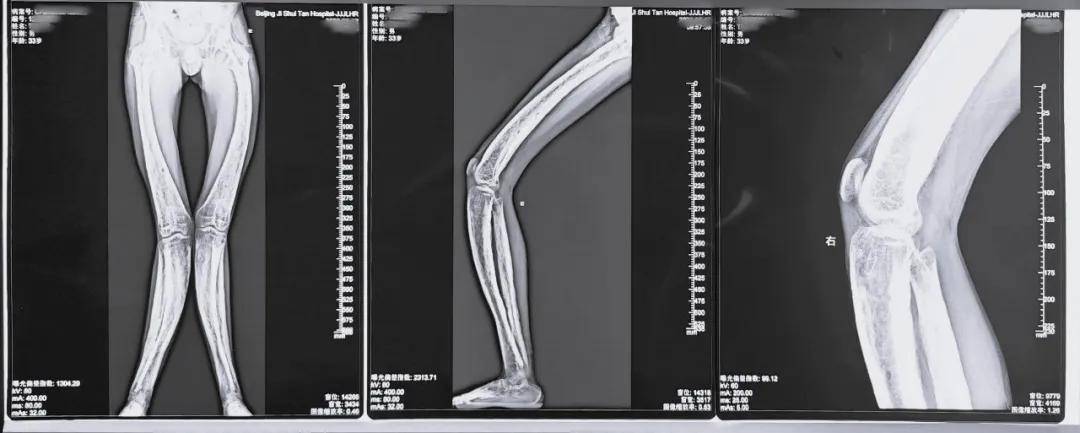

图说 / 小徐僵硬且弯曲的双腿

图说 / 小徐的术前影像资料